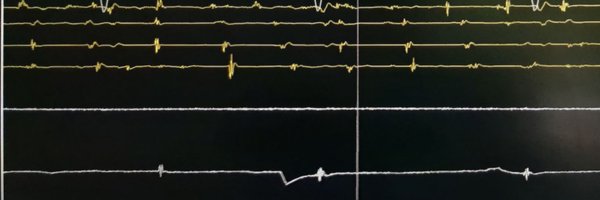

#DeepLearning algorithm for predicting left ventricular systolic dysfunction in #Afib with rapid ventricular response https://t.co/9HimHeCE4i #EHJDigital #ArtificialIntelligence @BruiningNico @rafavidalperez @GerdHindricks @rbcasado